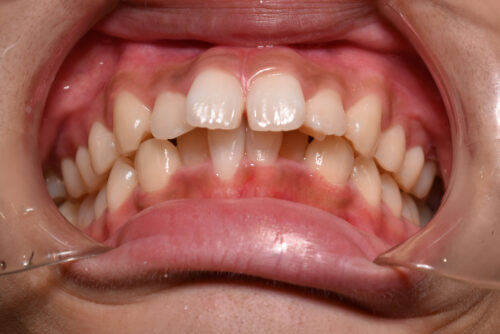

ワイヤー矯正治療7か月後です。

本症例のように

歯科矯正用アンカースクリュー(デュアル・トップオートスクリュー)を利用し

下顎のオートローテーションを行うことで

歯を抜かない非抜歯矯正治療でも

E-lineを整えることができます。